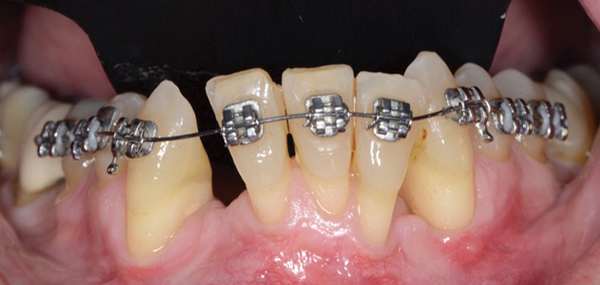

Tooth Movement into Compromised Bone Areas Orthodontic tooth movement may sometimes be performed in patients with partially edentulous dentitions hav-. It should be reimplanted within 2 hours and stabilized with a dental dressing paste. By applying slight pressure to a tooth the bone on the forward side will reabsorb while the bone on the reverse side will be reformed.

By applying slight pressure to a tooth the bone on the forward side will rebsorb while the bone on the reverse side will be reformed. If the tooth cannot be replaced for whatever reason store the tooth in the patients mouth in their saliva but avoiding biting the tooth as this will damage the periodontal ligament cells. Because bone deposition and reabsorption can occur and because bone responds to mechanical stress Wolffs law a tooth can be moved.

How can a tooth be moved in a bony socket during orthodontic treatment Answer from PSYCH 101 at Rutgers University Newark. By applying slight pressure to a tooth the bone on the forward side will reabsorb while the bone on the reverse side will be reformed. By applying slight pressure to a tooth the bone on the forward side will reabsorb while the bone on the reverse side will be.

By applying slight pressure to a tooth the bone on the forward side will reabsorb while the bone on the reverse side will be reformed. By applying slight pressure to a tooth the bone on the forward side will reabsorb while the bone on the reverse side will be. By applying slight pressure to a tooth the bone on the forward side will rebsorb while the bone on the reverse side will be reformed. How can a tooth be moved in a boney socket during orthodontic treatment. The bone is slightly damaged and a tooth can be moved easier in this damaged zone. How can a tooth be moved in a boney socket during orthodontic treatment. By applying slight pressure to a tooth the bone on the forward side will reabsorb while the bone on the reverse side will be reformed. Please log in or register to add a comment. By applying slight pressure to a tooth the bone on the forward side will reabsorb while the bone on the reverse side will be reformed.